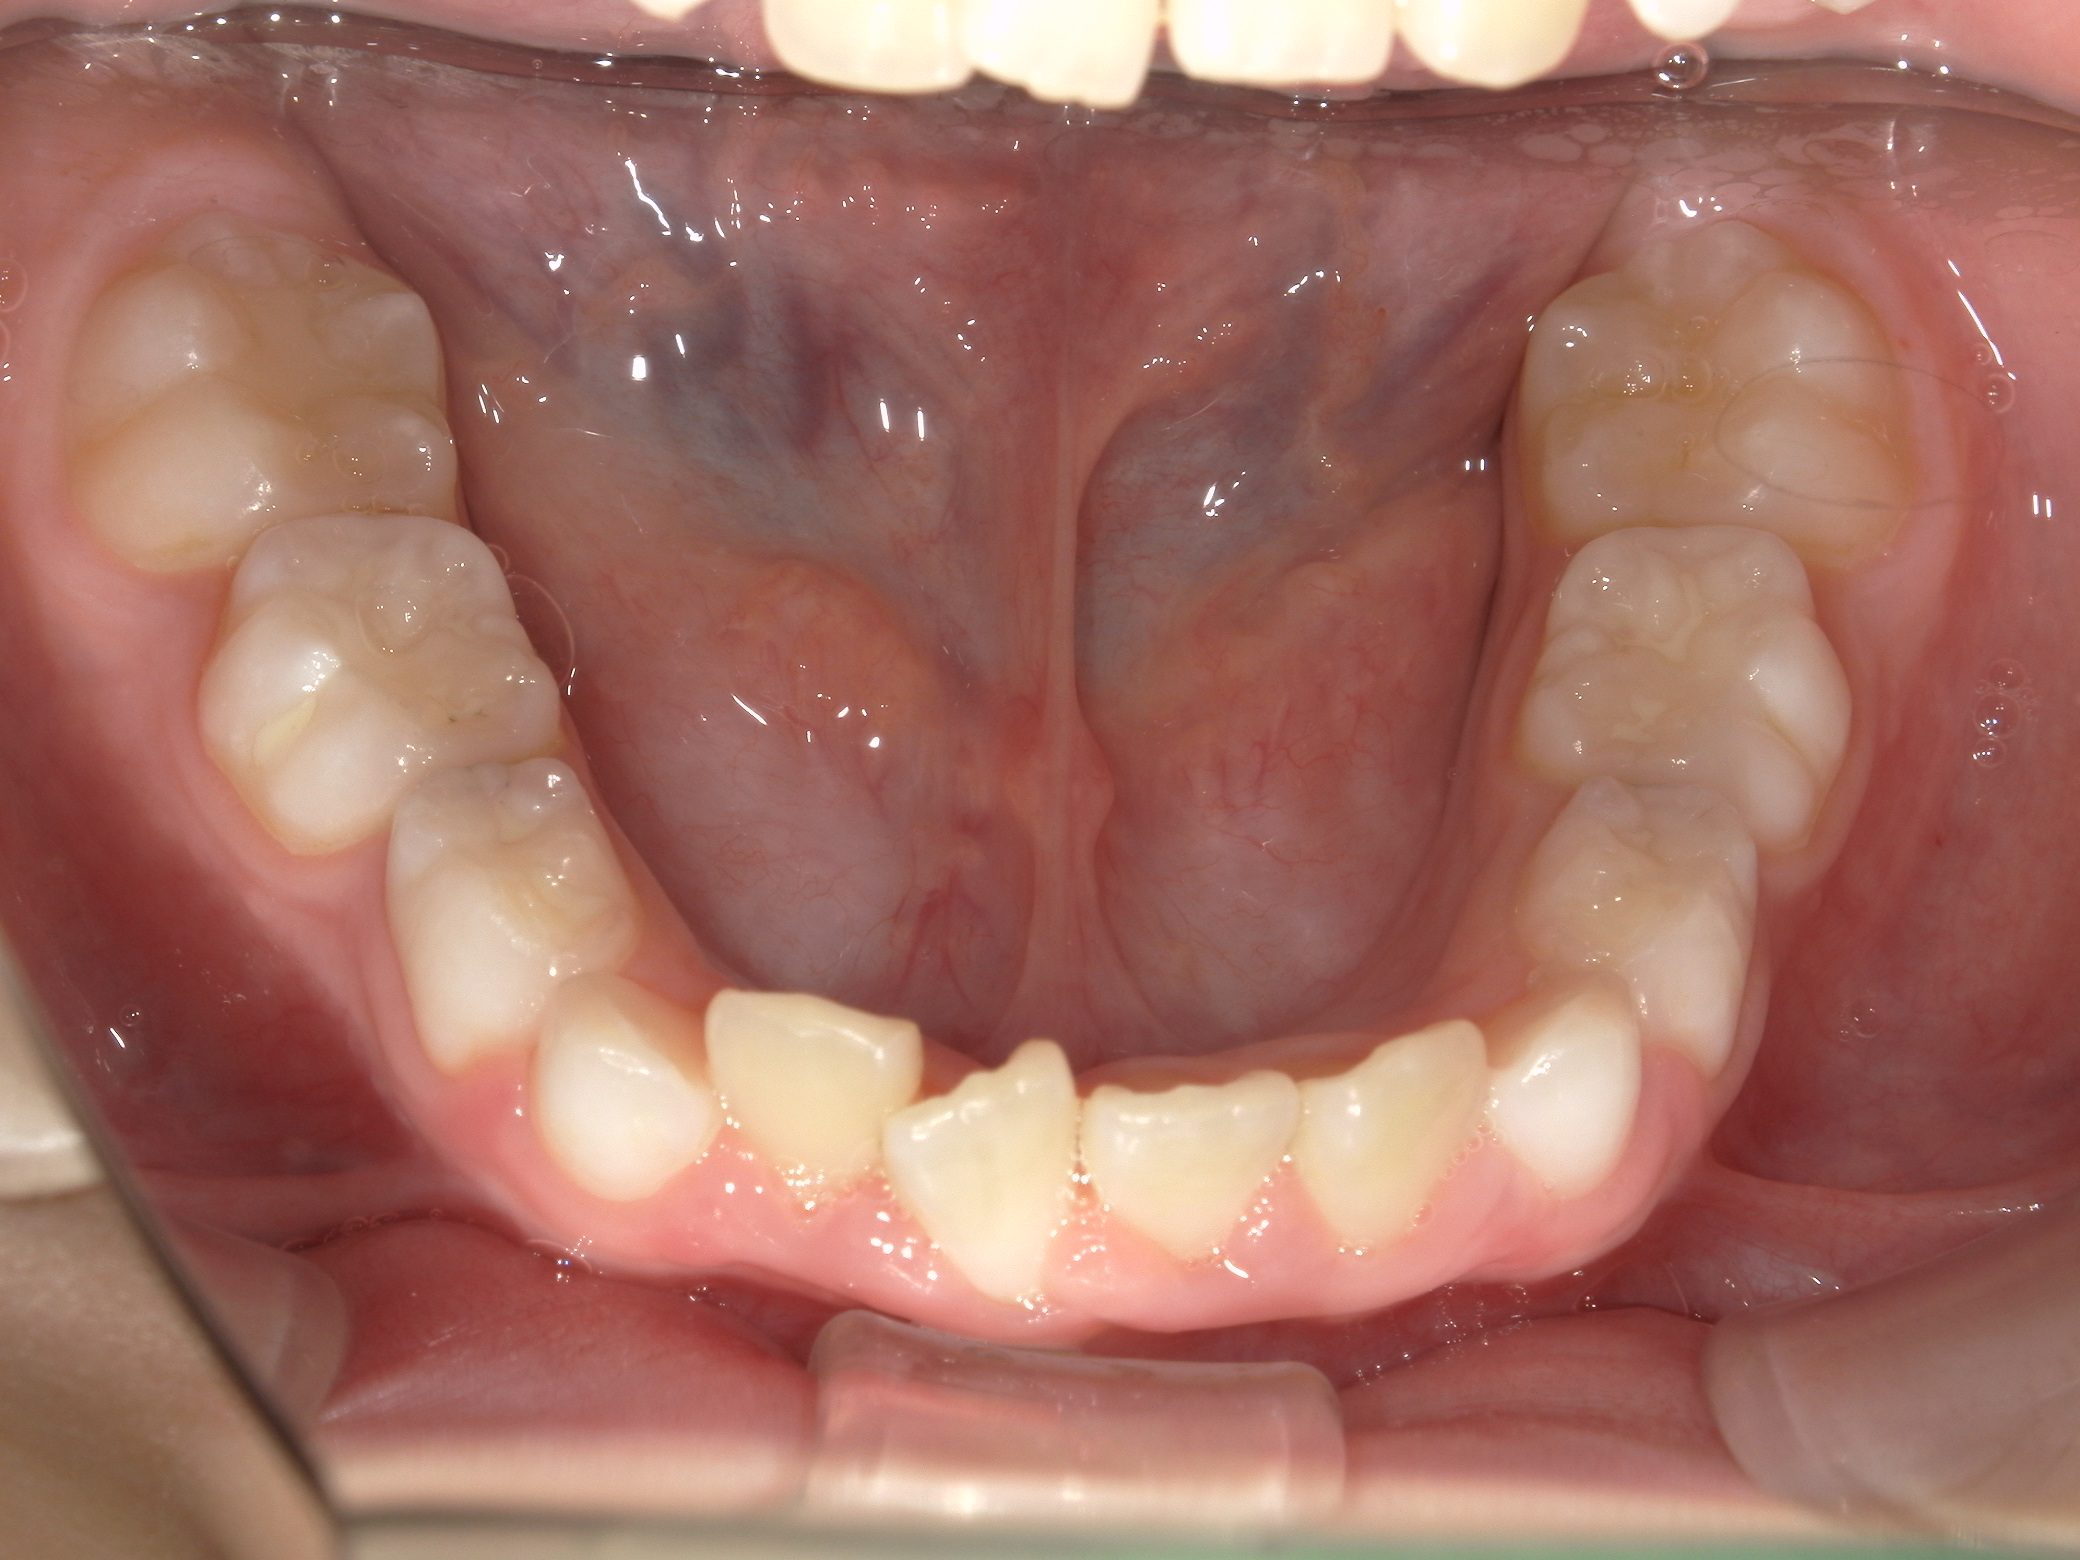

【小学生】 8歳 インビザライン矯正 過蓋咬合(深い咬み合わせ)と叢生(でこぼこ)を改善

小学生で開始

インビザライン ファースト

でこぼこ

非抜歯

1期治療のみで改善

Before

After

治療期間

1年4カ月年

治療開始

8歳

種類

インビザライン矯正

使用装置

インビザラインファースト(こどものインビザライン)

コメント

転勤族ということもあり、時間に制限がありましたが、患者さんがしっかり装置をつけてくれたので お引越しまでに終了することができました。

途中 側方の歯がどんどん生え変わって 最終的には全部永久歯で終了しました。

咬み合わせが深い場合、インビザラインファーストは咬み合わせを浅くするのに適しています。